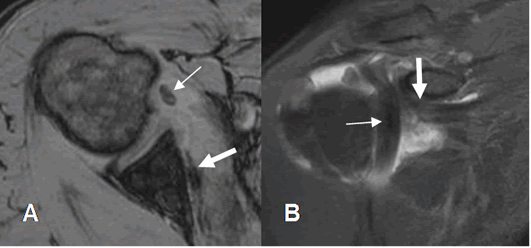

Fig 156. Luxación del biceps.

A: RM axial en FFE y B: RM coronal en STIR. “Luxación” medial de la cabeza larga del biceps. (Flecha delgada), con ruptura retraída del tendón del subescapular. (Flecha gruesa).